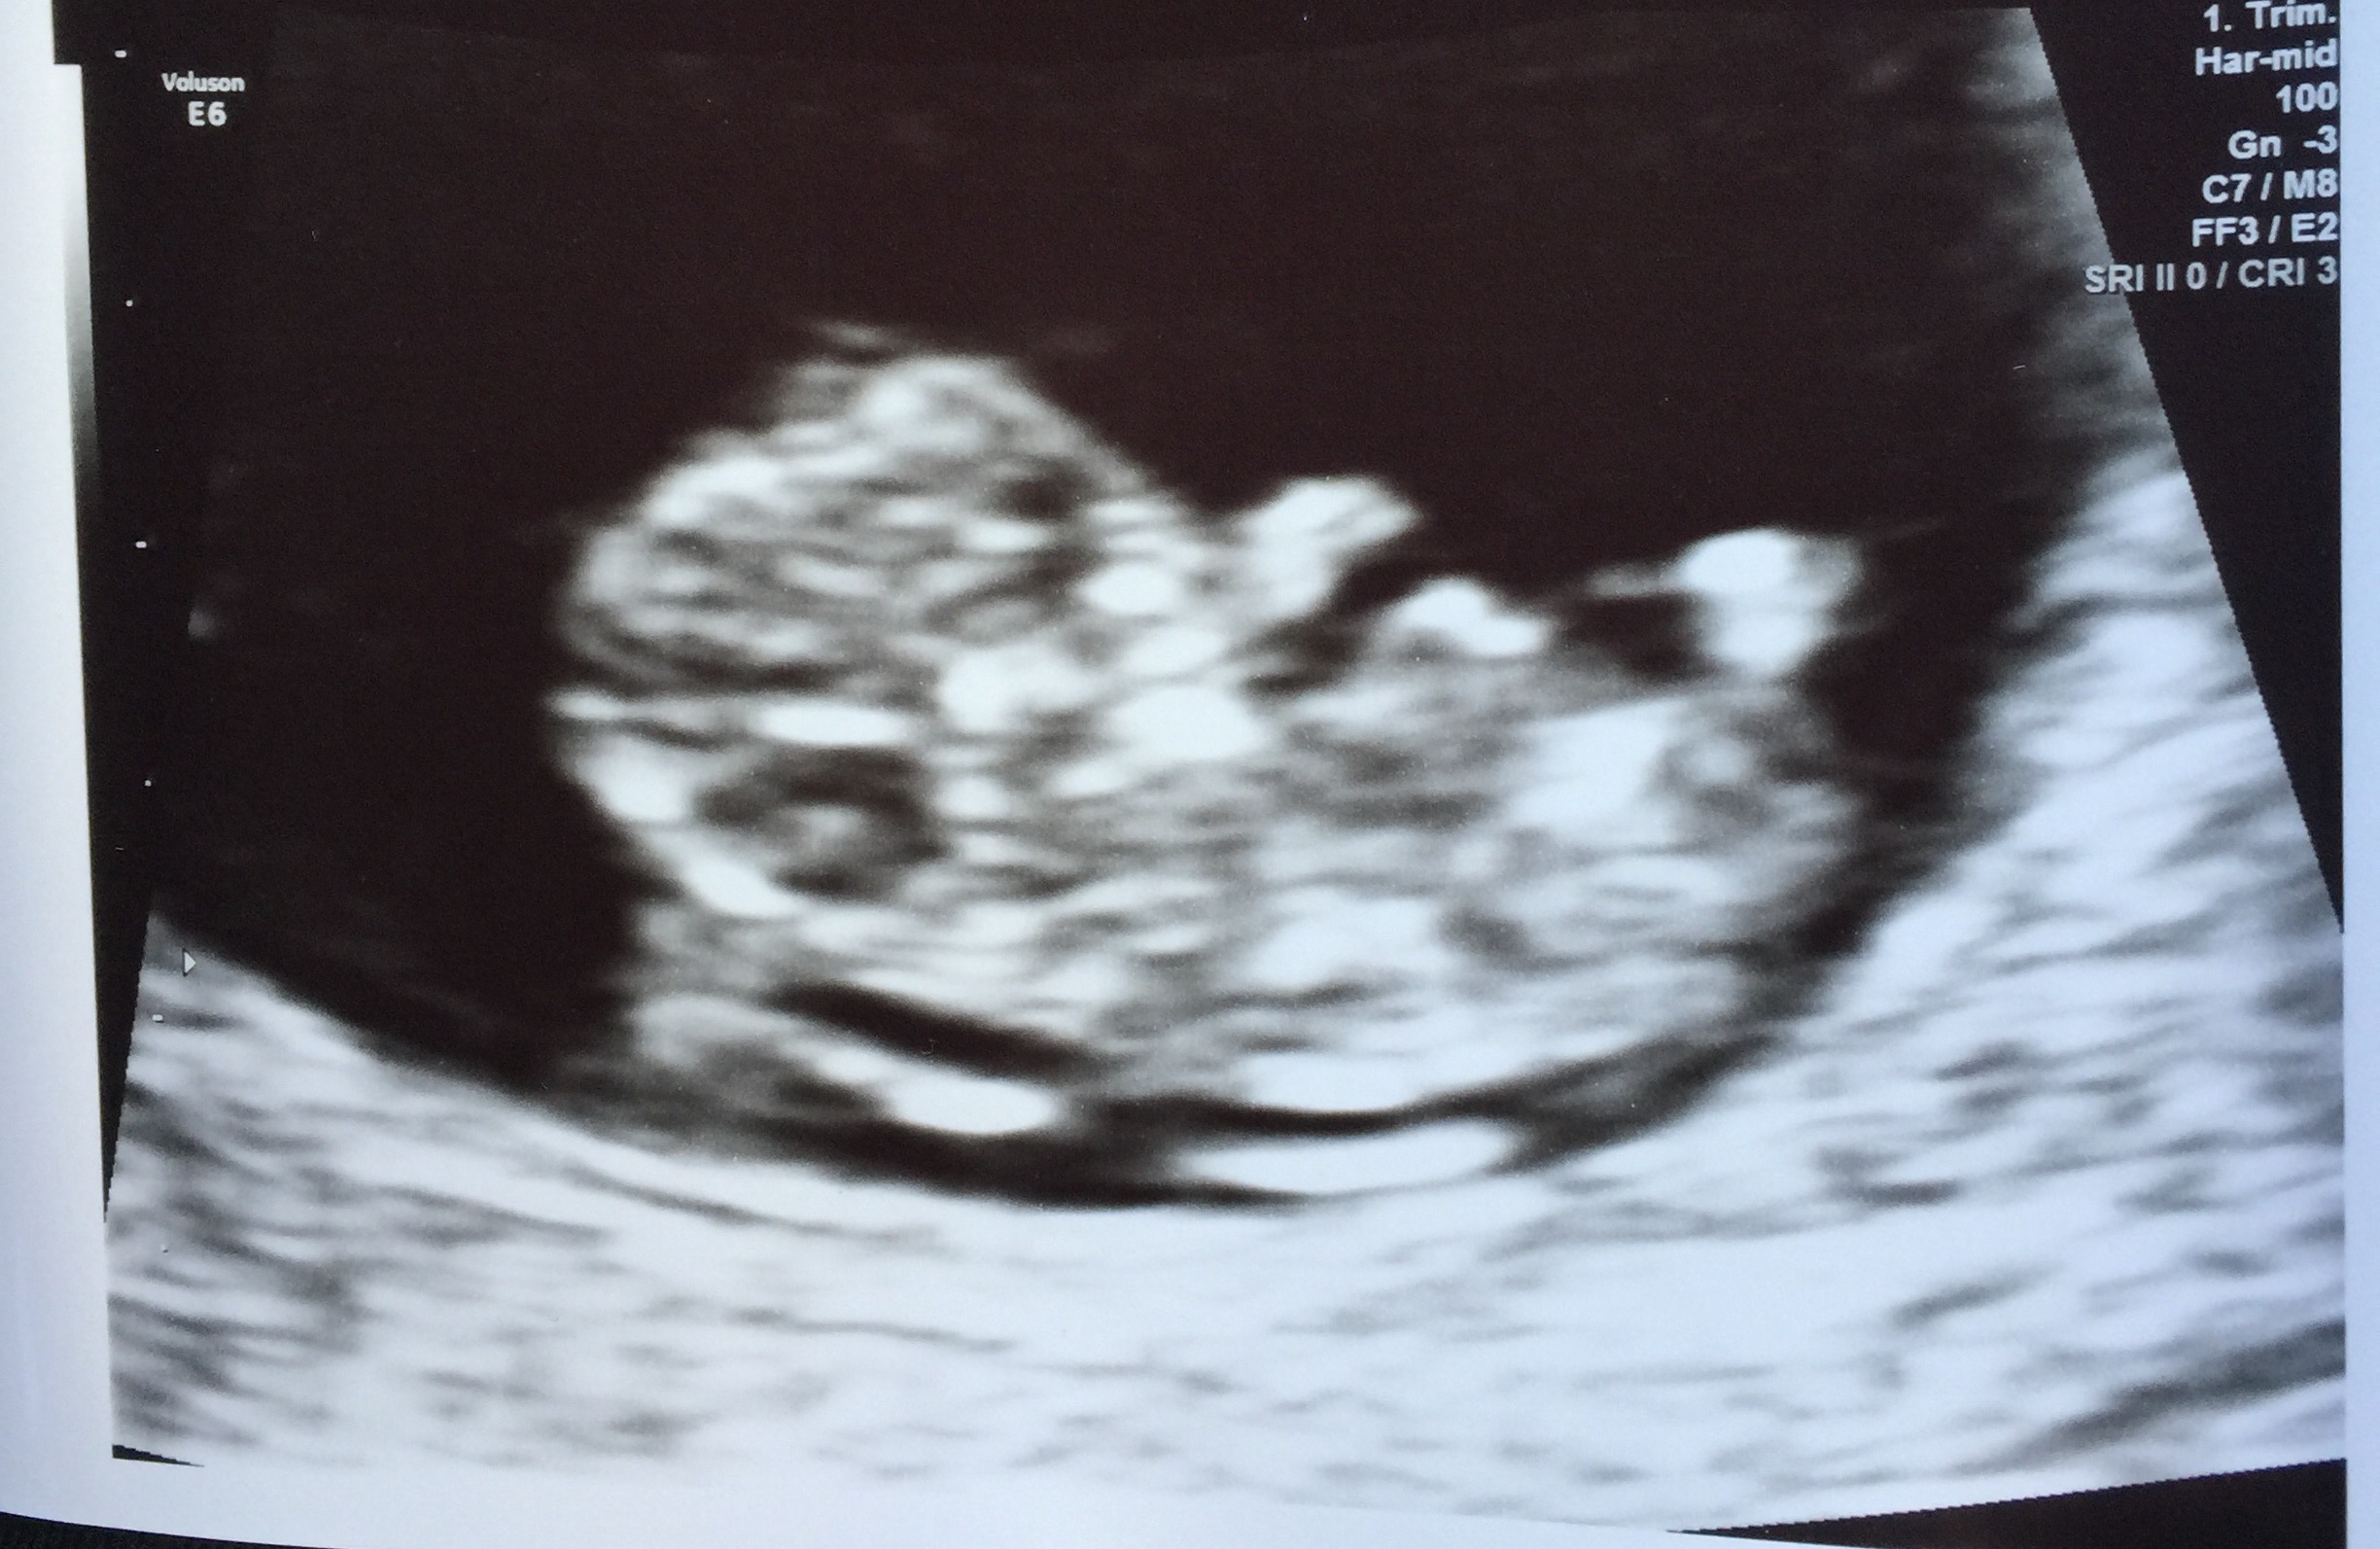

Baby has grown so much!!! It's no longer a little peanut like when we saw it for the first time at 6w3d. Today at 10w3d he/she was waving and kicking the feet around, heartbeat of 160 something. My heart is bursting with love for this precious little life.

Here's our nugget at 10w!!! So happy to see he/she moving around and the little heartbeat at 160BPM (Sorry had an error with the above post not sure how to delete it)